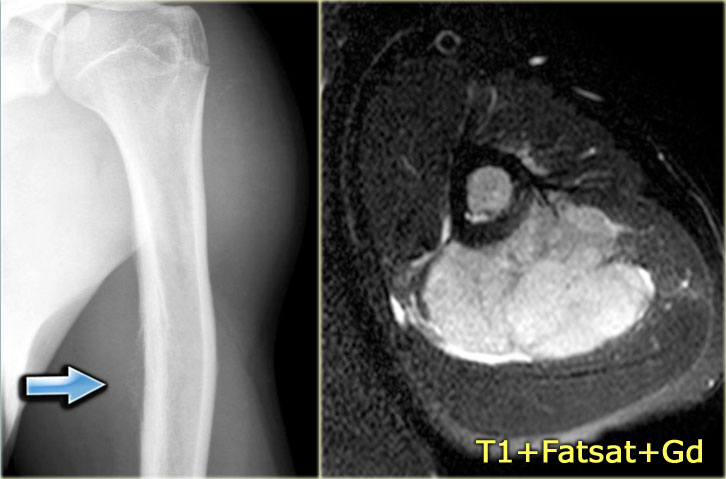

ABC (8)

On the left another ABC, located in the distal femur.

The plain radiograph shows a layered periosteal reaction and Codman triangle in direct relationship to an expansile lytic lesion with a thin peripheral bone shell.

CT also reveals the subperiosteal origin of the lesion with secondary involvement of the cortical bone.

Axial T2-weighted image with fatsat and contrast enhanced T1-weighted image with fat sat show multiple fluid-fluid levels with rim enhancement of the cavities filled with blood.

This is typical for an aneurysmal bone cyst.